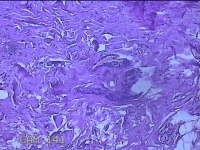

右手掌肿物

性别

女

年龄

32岁

临床诊断

1.右手掌肿物性质待查?右腕管综合征

一般病史

发现右手掌肿物疼痛伴拇示中指感觉迟钝约6年。

标本名称

大体所见

灰白粉红色肿物2.5x2x0.8cm一个,表面光滑,切开肿物呈实性,切面灰白粉红色,质软。